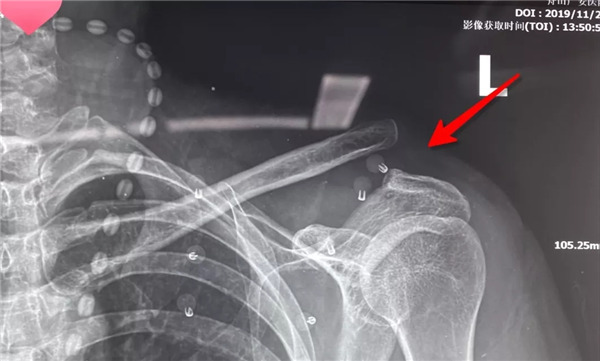

術(shù)前拍片--患者的肩鎖關(guān)節(jié)脫位屬于Rockwood  5型脫位

由于楊女士肩鎖關(guān)節(jié)脫位屬于Rockwood 5型脫位,廣安醫(yī)院危立軍副院長會診后建議楊女士的肩鎖關(guān)節(jié)脫位進(jìn)行手術(shù)復(fù)位固定。